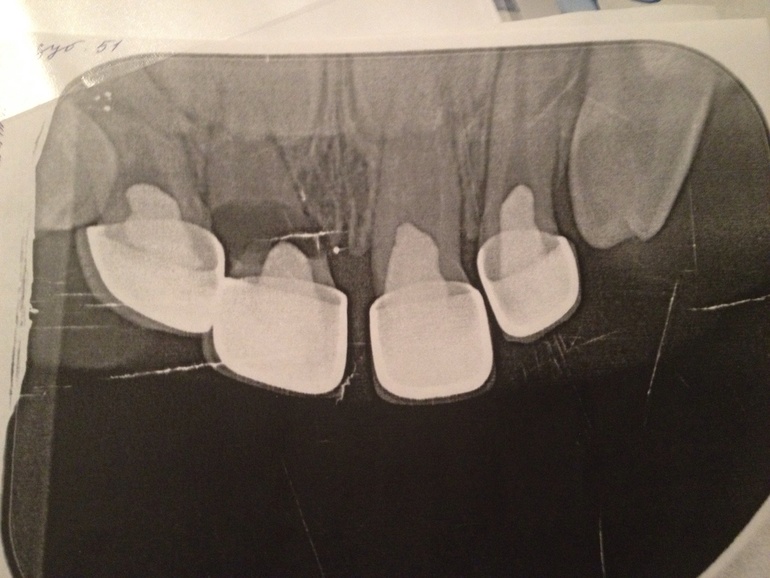

Прошу у вас совета. Сейчас сыну 2 года и 9 месяцев. Чуть меньше года назад поставили коронки на 4 верхних зуба. Недавно заметила шатание одного из зубиков. Выяснилось, что где-то сын стукнулся и сломал зубик.

Есть ли возможность как-то его сохранить?

Снимок прилагаю

Здравствуйте.К сожалению, данный зуб восстановить будет оооочень сложно. Нужно убрать коронку и посмотреть, в каком состояние находится зуб. Если корень достаточно плотный- можно попробовать его сохранить, но не покрывать коронкой, а как бы просто нарастить культю для сохранности места.Или, если плохо.... Удалить.И нужно внимательно рассмотреть рядом стоящий второй резец, что-то он тоже не очень...